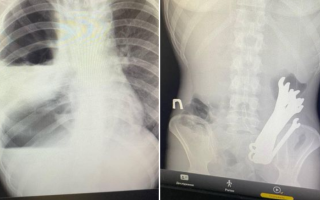

У Черкасах медики виявили у шлунку чоловіка шість гайкових ключів, фото

08:38, 25 вересня 2024 -